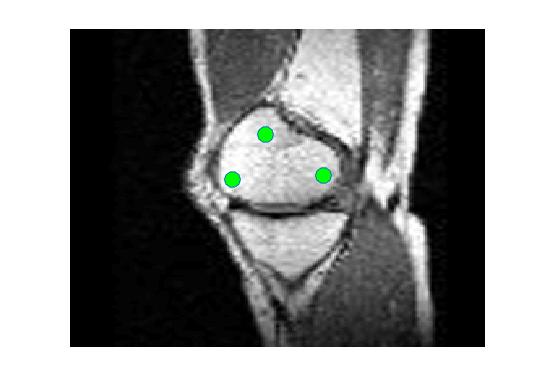

Four sets of test results are shown below. In Test 1 we compare models M1 – M6 to the proposed model M7 for two images which are hard to segment. The first is a CT scan from which we would like to segment the lower portion of the heart, the second is an MRI scan of a knee and we would like to segment the top of the Tibia. See Figure 9 for the test images and the marker sets used in the experiments. In Test 2 we will review the sensitivity of the proposed model to the main parameters. In Test 3 we will give several results achieved by the model using marker and anti-marker sets. In Test 4 we show the initialisation independence and marker independence of the Geodesic Model on real images.

Test 2 – Test of M7’s sensitivity to changes in its main parameters. In this test we demonstrate that the proposed Geodesic Model is robust to changes in the main parameters. The main parameters in (20) are and . In all tests we set , which is simply a rescaling of the other parameters, and we set . In the first example, in Figure 12, we compare the TC value for various and values for segmentation of a bone in a knee scan. We see that the segmentation is very good for a larger range of and values. For the second example, in Figure 13, we show an image and marker set for which the Spencer-Chen model (M3) and modified Liu et al. model M6 cannot achieve the desired segmentation for any parameter range, but which can be attained for the Geodesic Model for a vast range of parameters. The final example, in Table 1, compares the TC values for various values with fixed parameters and . We use the images and ground truth as shown in Figures 12 and 13: on the synthetic circles image we obtain a perfect segmentation for all values of tested, and in the case of the knee segmentation the results are almost identical for any , above which the quality slowly deteriorates.

Test 4 – Initialisation and Marker Set Independence. In the first example, in Figure 16, we see how the convex Geodesic Model M7 gives the same segmentation result regardless of initialisation, as expected of a convex model. Hence the model is flexible in implementation. From many experiments it is found that using the polygon formed by the marker points as the initialisation converges to the final solution faster than using an arbitrary initialisation. In the second example, in Figure 16, we show intuitively how Model M7 is robust to the number of markers and the location of the markers within the object to be segmented. The Euclidean distance term, used in the Spencer-Chen model M3, is sensitive to the position and number of marker points, however, regardless of where the markers are chosen, and how many are chosen, the geodesic distance map will be almost identical.